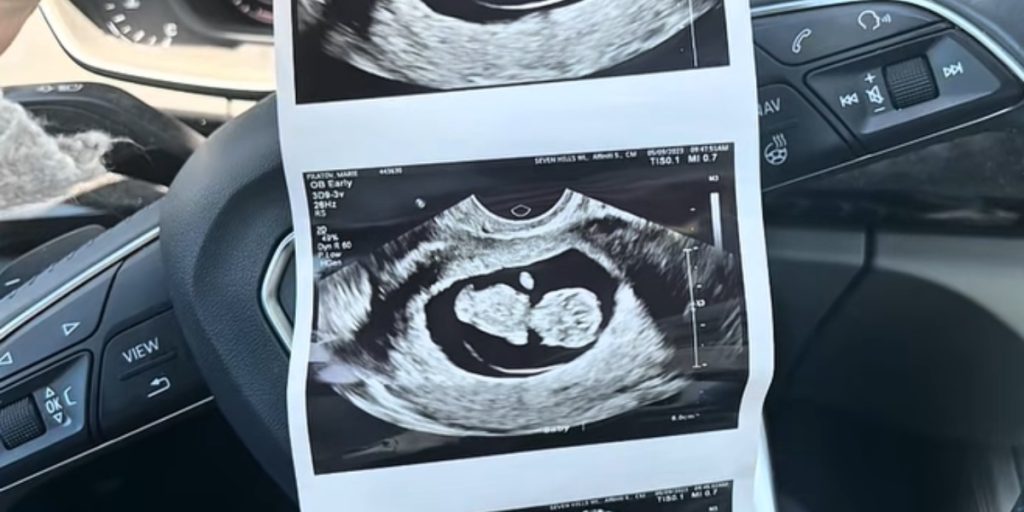

En mor har fortalt om det øjeblik, hvor en rutinemæssig graviditetsscanning pludselig tog en chokerende drejning.

Den 25-årige Marie Filatov fra Cincinnati delte en video på TikTok under brugernavnet @mariemomlife, hvor hun fortalte om sin graviditet med datteren Myla i 2022. Videoen er hurtigt blevet set mere end 430.000 gange.

“Jeg var så glad for at skulle have mit første barn med min forlovede Jack. Alt virkede som en helt normal graviditet, indtil vi skulle til 20-ugers-scanningen,” fortæller Marie til Newsweek.

Scanningen, der normalt er en rutinemæssig undersøgelse midt i graviditeten, blev for Marie en langt mere uventet oplevelse. Hun husker tydeligt, hvordan lægen på scanningen vendte sig mod dem og sagde noget, der chokerede dem.